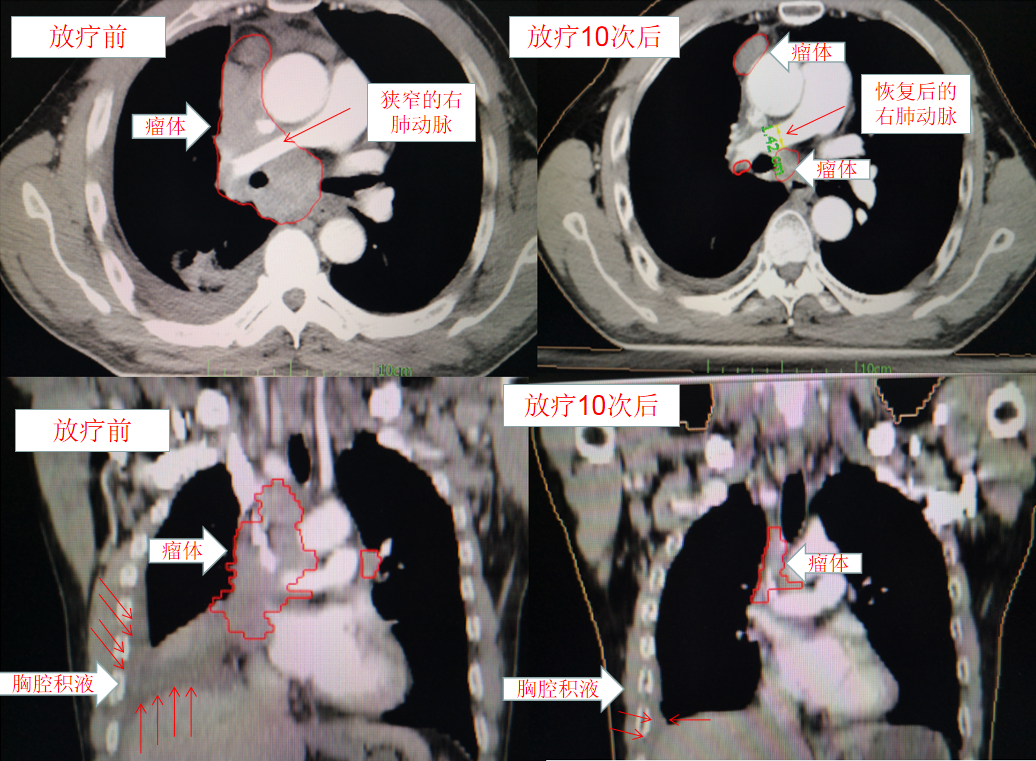

肺癌患者上(shàng)腔靜脈壓迫綜合征危及生(shēng)命時(shí)治療前後對比:

經過10次放(fàng)療後患者上(shàng)腔靜脈壓迫及肺動脈壓迫症狀明顯緩解,救患者生(shēng)命于危急關(guān)頭,後續繼續完成姑息性放(fàng)療,現(xiàn)患者定期複查及治療中。